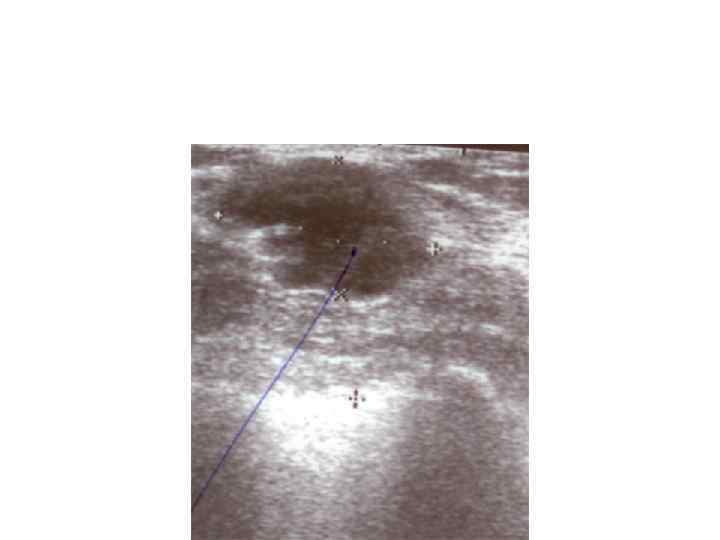

Диагностика 1 Самообследование 2 Профосмотры 3 Маммография 4 УЗИ 5 Термография Все случаи объемных Диагностика 1 Самообследование 2 Профосмотры 3 Маммография 4 УЗИ 5 Термография Все случаи объемных образований в молочных железах – показания к пункционной или эксцизионной биопсии.

Пункционная биопсия Пункционная биопсия